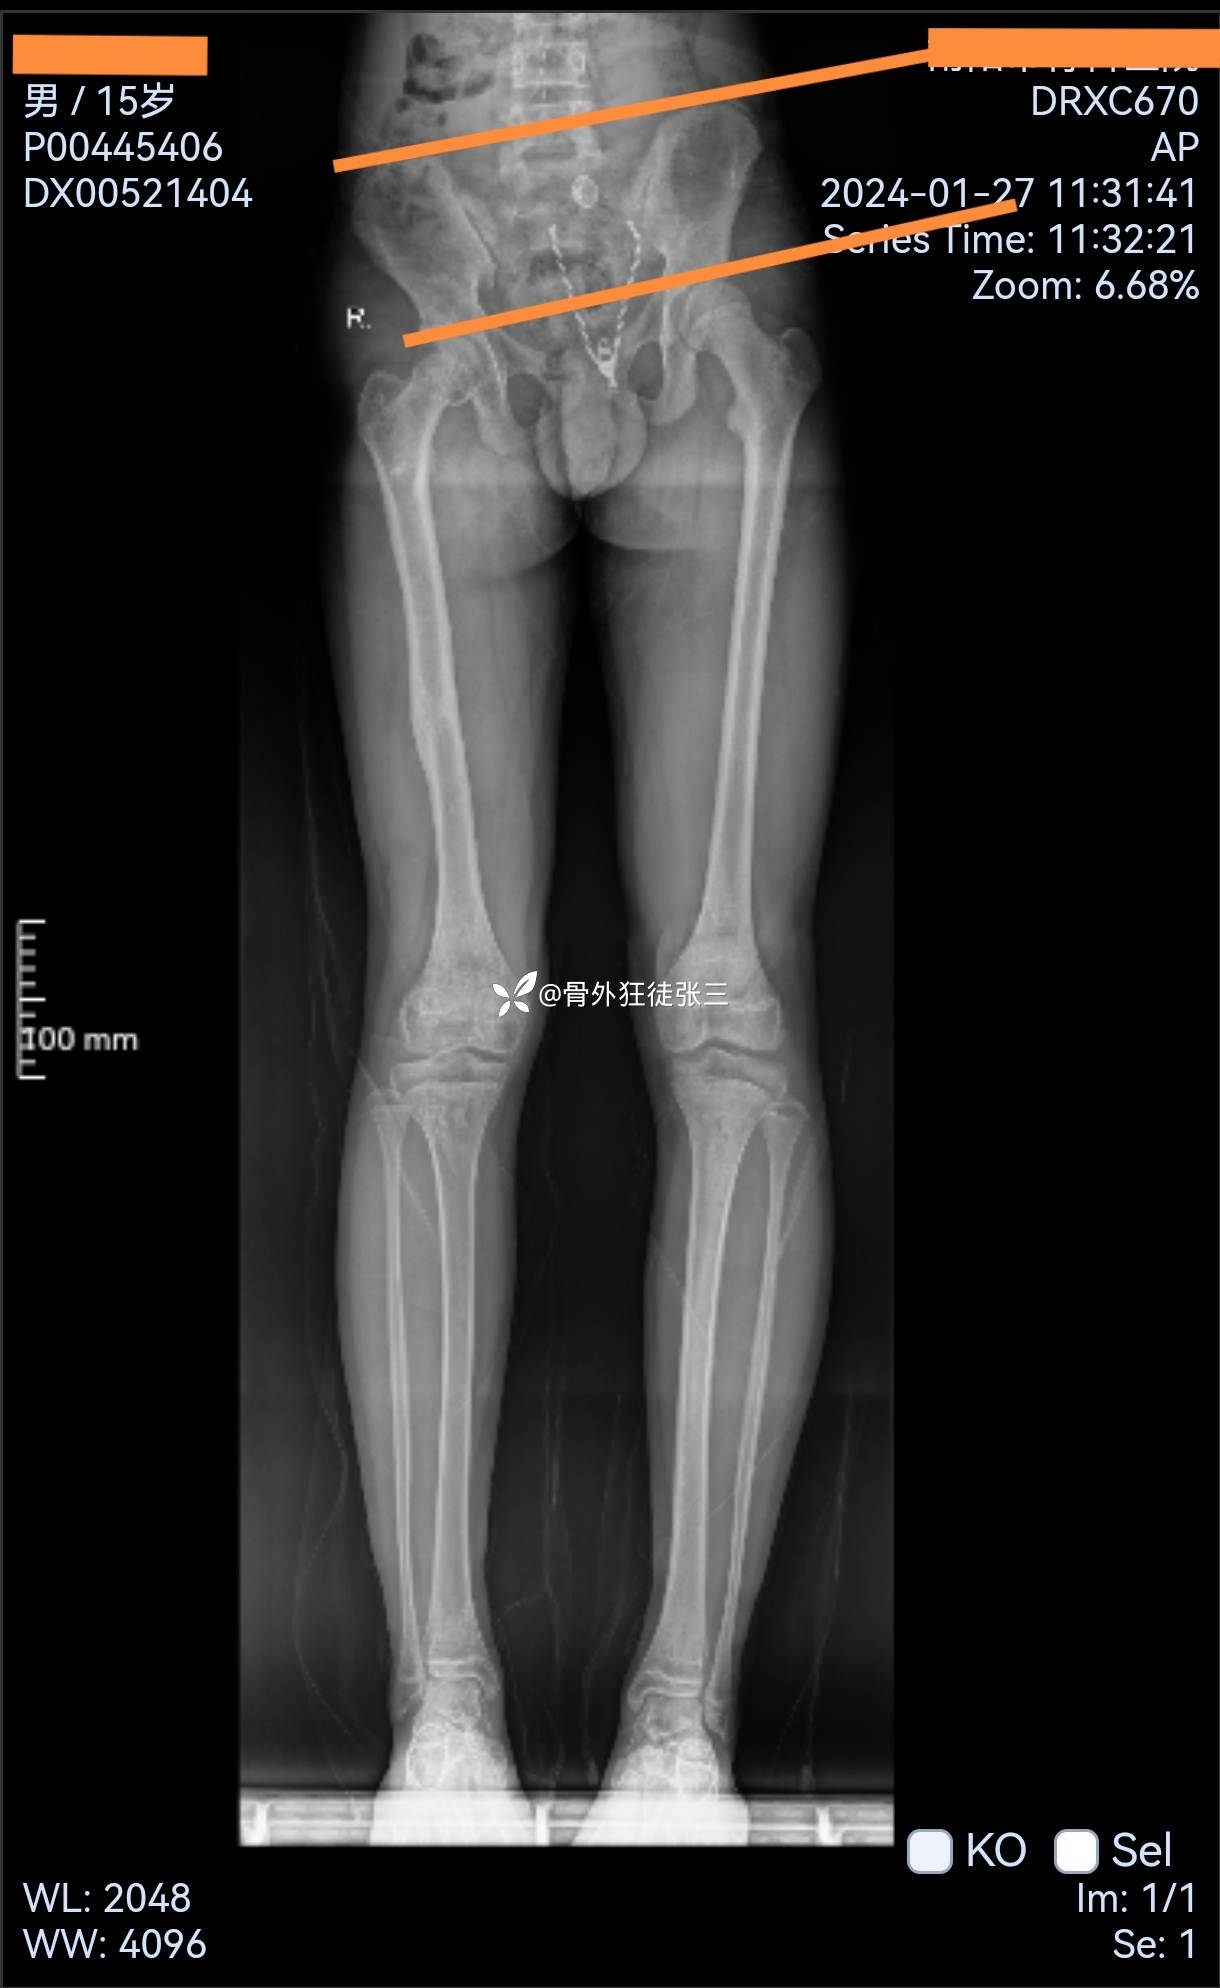

主诉:右下肢骨折术后肢体短缩2年。

2年前因“右股骨干骨折”在当地医院行“弹性髓内针+外架+石膏固定术”术后半年拆外架,1年拆弹性髓内针。目前左下肢短缩约4cm,为求治疗来院。

一,患侧发育延迟,原因?

损伤导致?外架阻滞原因?

1,目前处理,骨骺尚未愈合,好处是,预防骨盆倾斜、脊柱截侧弯,单边外架骨搬移?

缺点就是,后期可能拆了外架以后,再次短缩。

2,等骨骺完全闭合再截骨搬移,脊柱可能畸形。得不偿失